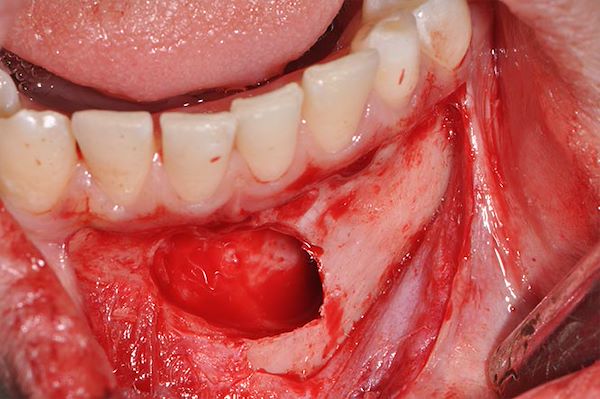

Estrazione canino in inclusione ossea vestibolare

Intervento realizzato da: Stefano Daina

OPT pre-intervento,Pre-estrazione di canino inferiore in inclusione ossea vestibolare,Incisione e scollamento del lembo,Corona del canino dopo aver eseguito osteotomia,Sito post-estrattivo,Dente estratto di lunghezza 27 mm,Sutura a fine intervento